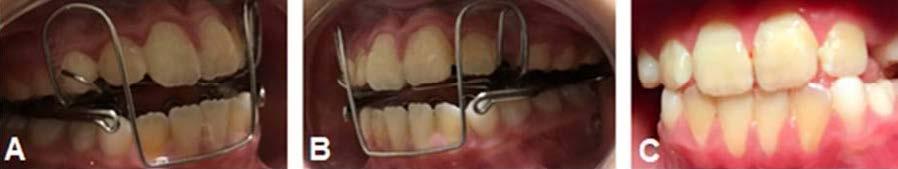

Sus citas fueron mensuales hasta la obtención de resultados favorables 8 meses después. Consiguiendo cerrar la mordida y obteniendo una línea dental favorable, terminando tratamiento con su aparato removible SN6 en noviembre del 2022 (Figura 4). Se dio de alta temporal, retirando su aparatología funcional.

en julio del 2024, acude la paciente 20 meses después a su cita de control, donde se encontró su línea

media dental estable, así como su mordida anterior manteniendo un overbite favorable, sin presentar indicios de recidiva de mordida abierta anterior, por lo cual se inició su tratamiento en el 2022 (Figura 5).

Figura 4. Resultados del SN6.

Figura 5. Valoración final, 20 meses después.